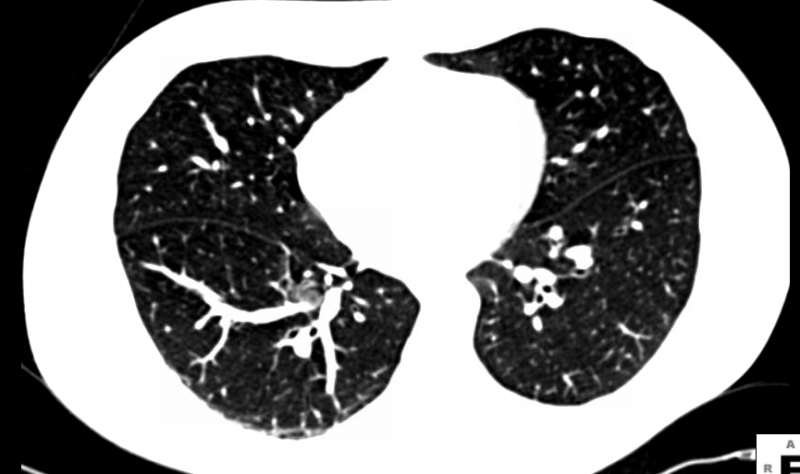

The American College of Radiology (ACR) is accepting applications for its new ACR Lung Cancer Screening Center program, which recognizes facilities committed to providing quality screening care to patients at the highest risk for lung cancer.

The American College of Radiology said it is deeply disappointed at the failure of the Medicare Evidence Development & Coverage Advisory Committee (MEDCAC) to vote in support of national Medicare coverage of low-dose computed tomography (LDCT) screening for patients at high risk for lung cancer.